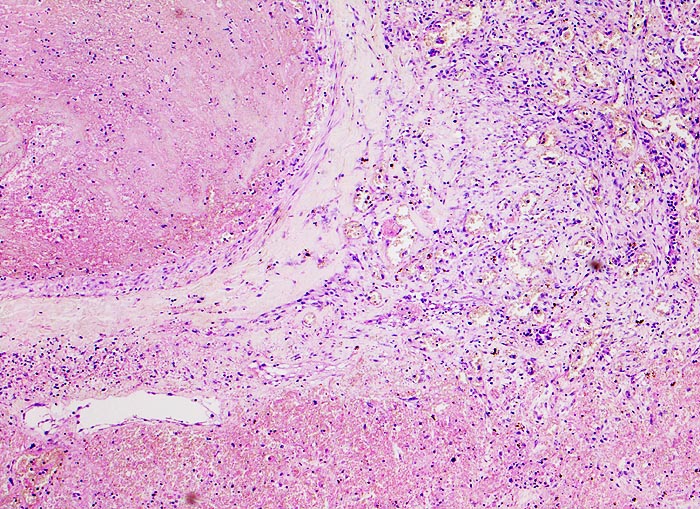

PathoPic ID 3562 - hämorrhagischer Lungeninfarkt bei Lungenembolie

hämorrhagischer Lungeninfarkt bei Lungenembolie

Links im Bild ein Pulmonalarterienast mit einem

frischen Embolus. Das Lungenparenchym rechts im Bild ist nekrotisch und stark hämorrhagisch.

Tiefe Beinvenenthrombosen bei metastasierendem Prostatakarzinom. Koronare Herzkrankheit.